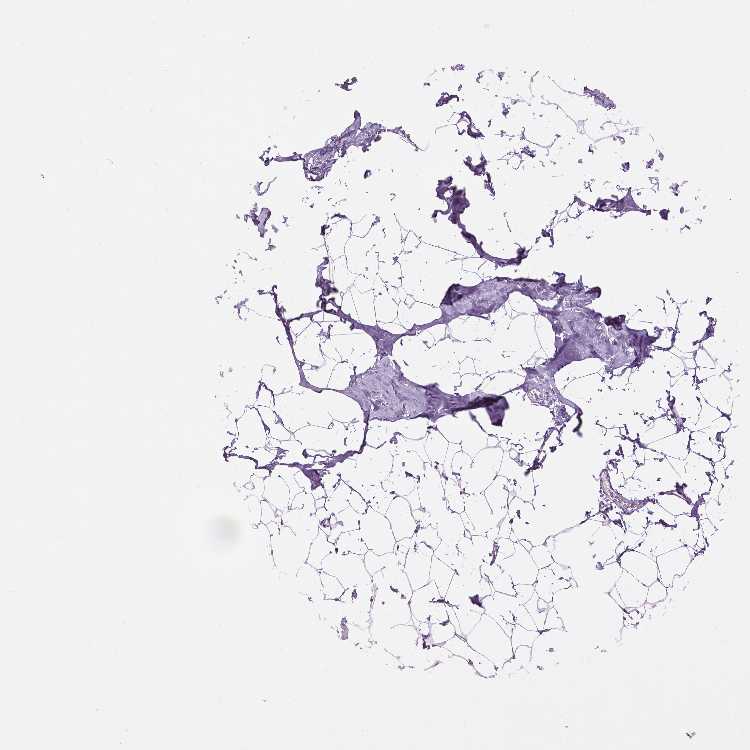

TISSUE PRIMARY DATA BREAST Show tissue menu

BREAST - Antibody stainingi

Antibody staining in the annotated cell types in the current human tissue is reported as not detected, low, medium, or high, based on conventional immunohistochemistry profiling in selected tissues. This score is based on the combination of the staining intensity and fraction of stained cells.

Each image is clickable and will lead to virtual microscopy that enables deeper exploration of all samples and also displays staining intensity scores, fraction scores and subcellular localization as well as patient and tissue information for each sample.

Antibody HPA001565Antibody HPA056092

Adipocytes Not detectedNot detected

Glandular cells Not detectedNot detected

Myoepithelial cells Not detectedNot detected